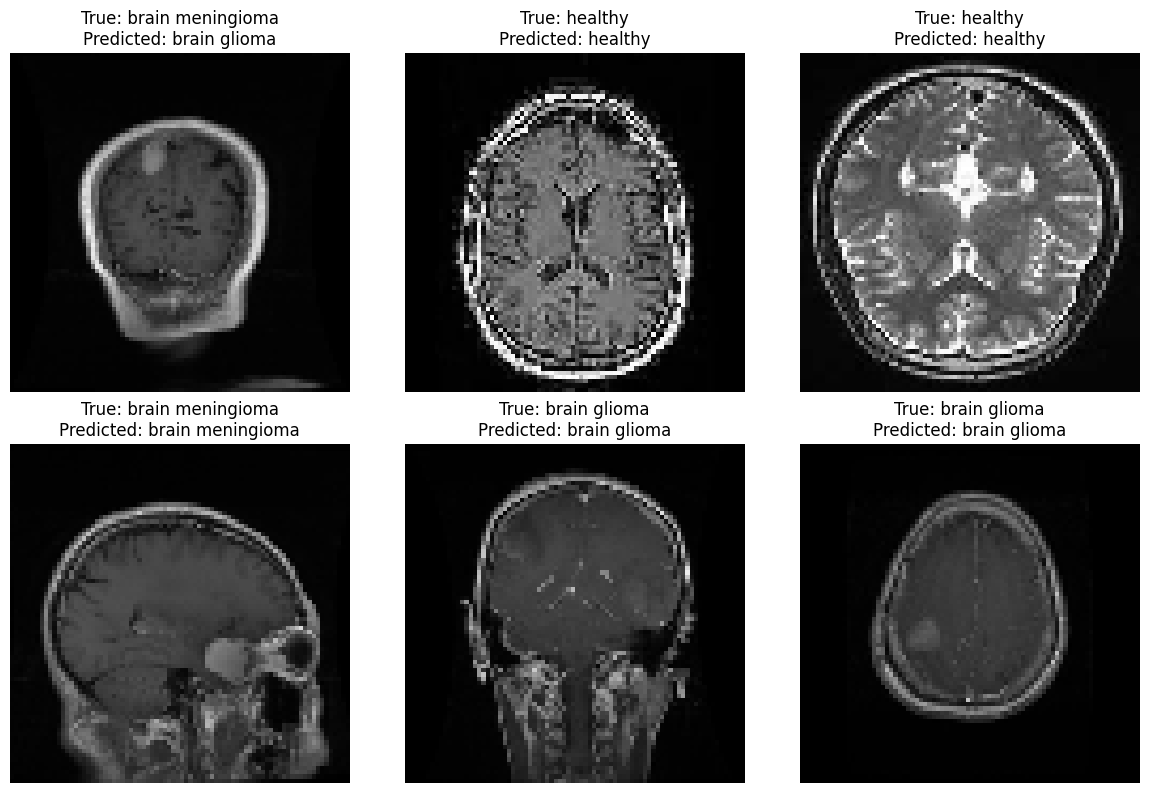

label_to_class = { 0: 'healthy', 1: 'brain glioma', 2: 'brain meningioma', 3: 'brain pituitary', } # Select a random subset of images to display num_images_to_display = 6 random_indices = np.random.choice(len(X_test), num_images_to_display, replace=False) # Create a figure and subplots fig, axes = plt.subplots(2, 3, figsize=(12, 8)) axes = axes.flatten() for i, index in enumerate(random_indices): image = X_test[index] true_label = y_test[index] predicted_label = np.argmax(predictions[index]) axes[i].imshow(image) axes[i].set_title(f"True: {label_to_class[true_label]}\nPredicted: {label_to_class[predicted_label]}") axes[i].axis('off') plt.tight_layout() plt.show()